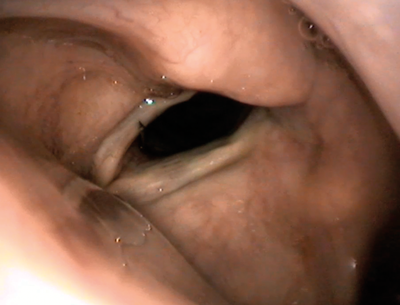

Figure 2. Endoscopic view of medialisation injection via thyrohyoid approach;

note the progressive bulking of the right vocal fold as the material is injected.

Figure 4. Endoscopic view of medialisation injection via cricothyroid approach.